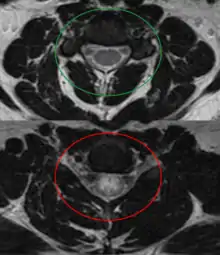

Axial T2 MRI of cervical spine demonstrating normal cord signal (green circle) and increased T2 signal in the central cord (red circle).